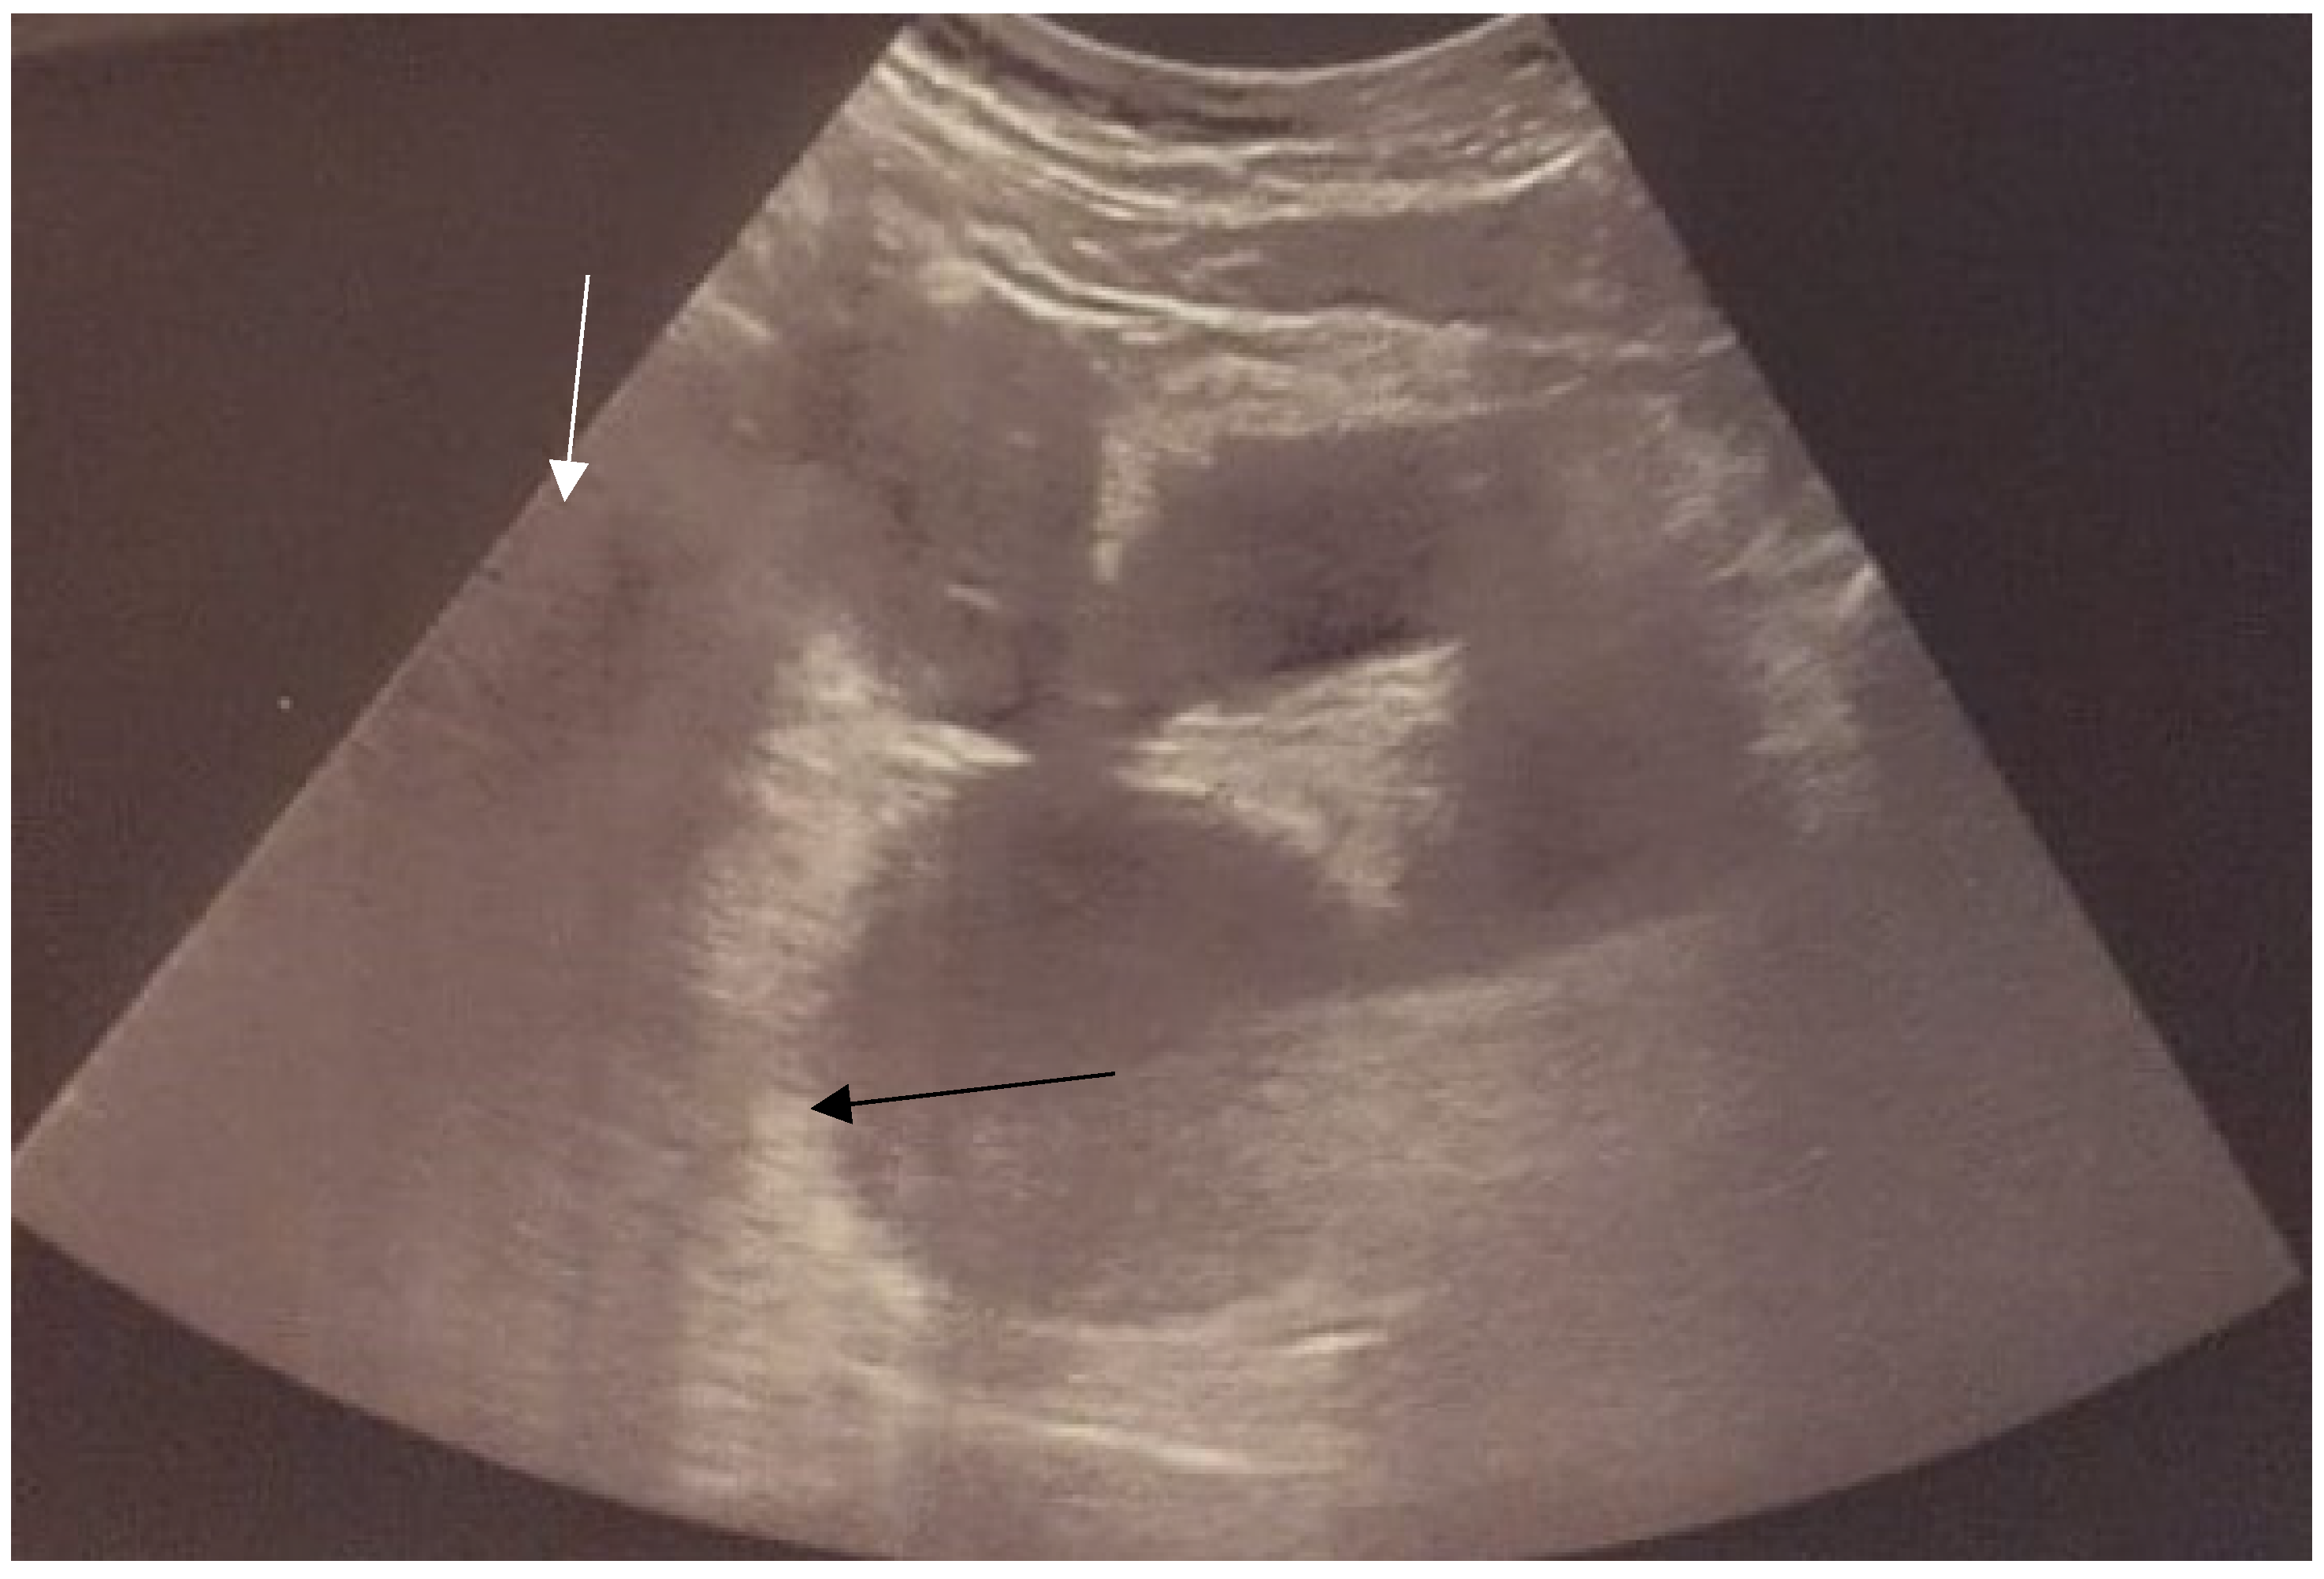

2.2. Preoperative Management